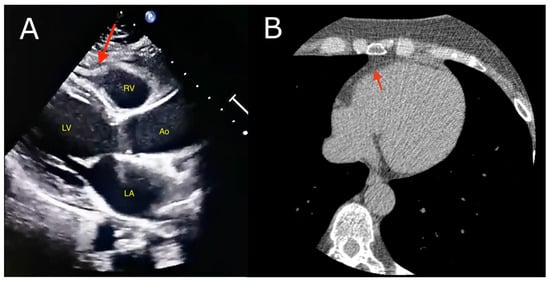

5.1.1. Echocardiography

5.1.2. Computed Tomography